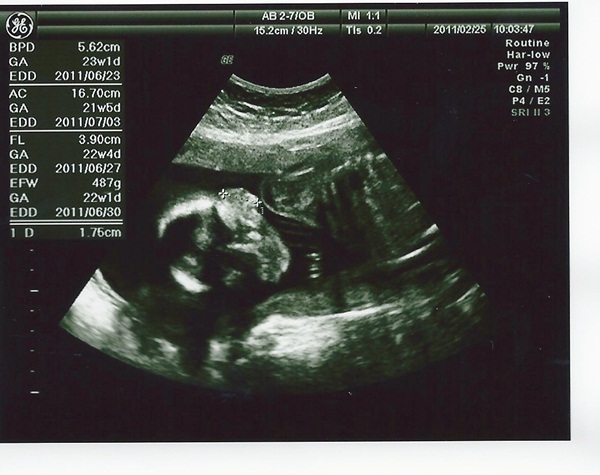

二寶

sophie

頭圍BPD:5.62

cm (4.08cm) 頭圍BPD:5.59cm

肚圍AC:

16.70 cm(11.79CM) 肚圍AC:15.77CM

大腿骨FL: 3.9

cm(2.31CM) 大腿骨FL:3.6CM

體重EFW: 487

g(193g ) 體重EFW:421g

關於媽媽的體重這次重了2公斤

明明就沒吃什麼

不過看到寶寶一切正常

我想2公斤就別在意了(從懷孕到現在總共重3公斤)